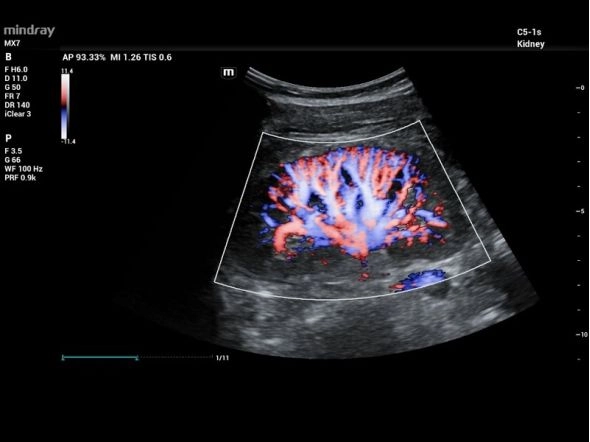

- Области применения: Абдоминальные исследования, Акушерство и гинекология, Кардиология, Сосудистые исследования, Неврология, Травматология и ортопедия, Урология, Эндокринология, Педиатрия, Неонатология, Транскраниальные исследования, Онкология

- Режимы: В-режим, М-режим, Цветное допплеровское картирование, Энергетический допплер, Импульсно-волновой допплер, цветной М-режим

- Виды допплеров: ЦДК цветовой, CWD постоянно-волновой допплер, Энергетический допплер, Импульсно-волновой допплер, Тканевой допплер

- PDI и DirPDI – энергетический и направленный энергетический допплер

- HR Flow – ЦДК высокого разрешения

Почесная перфузия